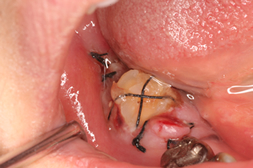

| 術中 |

2本の歯の移植を2回に分けて行いました

部分的な矯正で歯の位置や角度を直していきます |